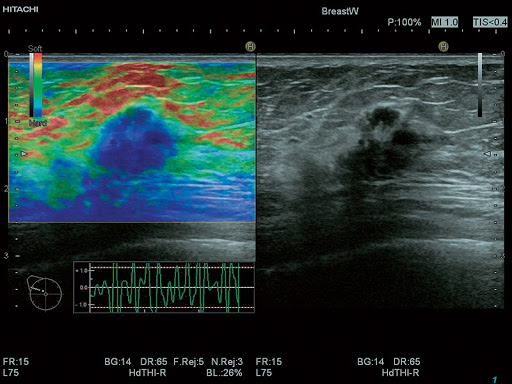

HI-RTE – эластография в режиме реального времени

- HdTHI – расширенная гармоника высокой четкости